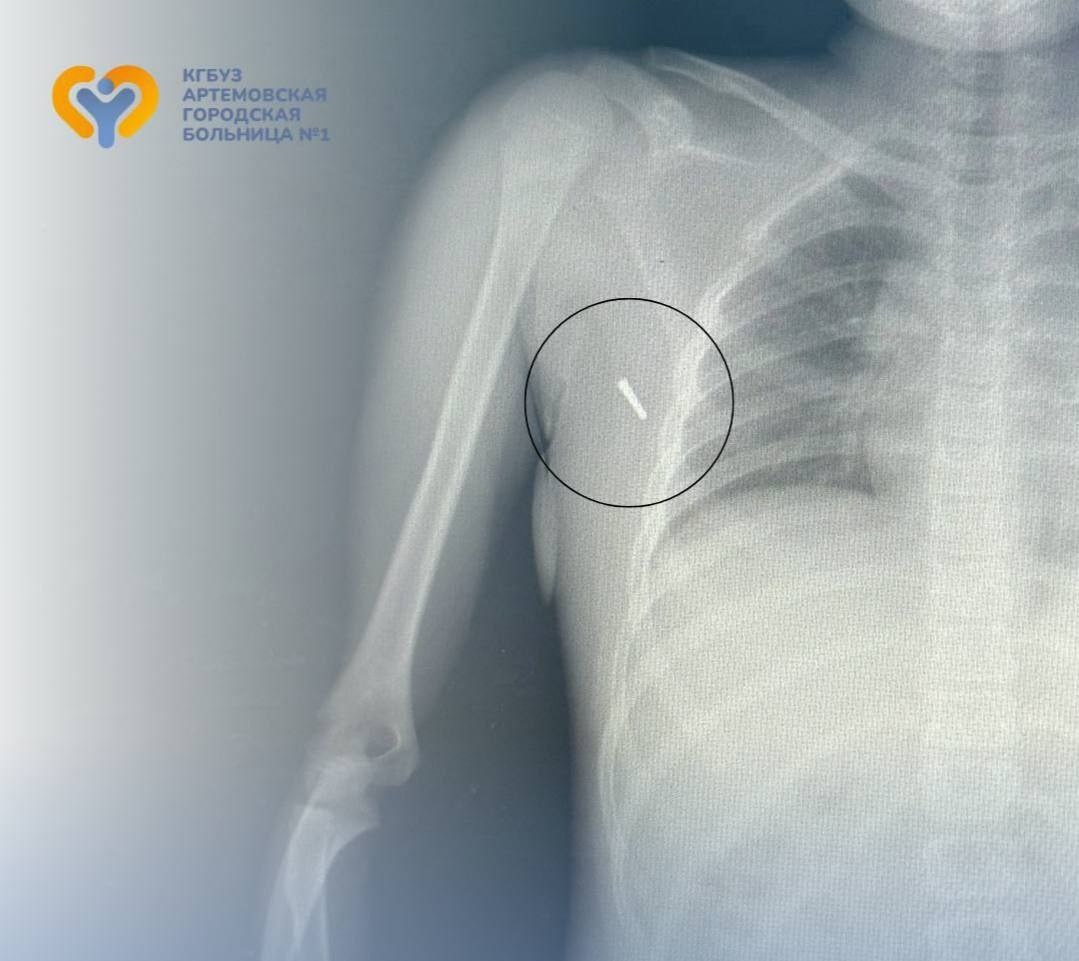

Врачи извлекли часть градусника из подмышки 8-летней девочки, пострадавшей в ДТП Вечером 18 июля в стационар поступила 8-летняя девочка с необычной травмой: во время поездки в машине у неё под мышкой находился ртутный термометр. В результате аварии наконечник градусника отломился и вошёл в мягкие ткани. Травматологи провели консультацию с токсикологами Владивостокской клинической больницы №2. Специалисты отметили: опасны пары ртути при вдыхании, а не само вещество в минимальных дозах, попавшее в ткани. Удаление можно провести безопасно. Хирурги успешно извлекли обломок, провели рентген-контроль и оставили ребёнка под наблюдением. Сейчас девочка чувствует себя хорошо и уже выписана домой.

Хирурги успешно извлекли обломок, провели рентген-контроль и оставили ребёнка под наблюдением.